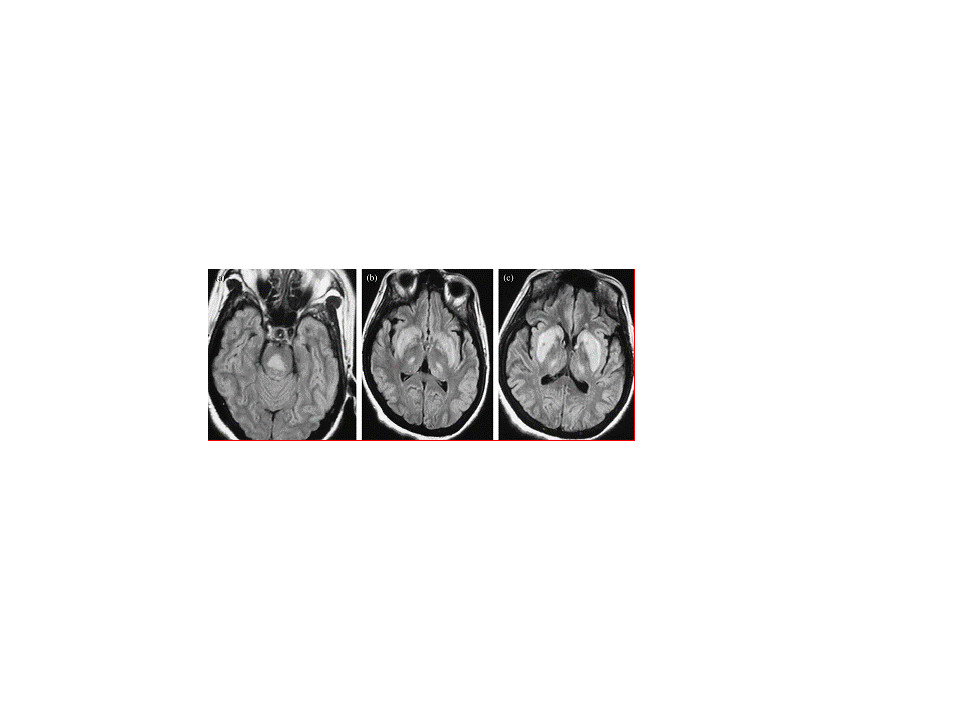

ODS在CT上表现为脑桥中央或脑桥外病灶处的低密度影,但CT不能反映疾病的真实程度,MRI能更好地反映病灶的数量和程度。早期可无异常,出现症状后1周DWI上可发现高信号。急性期表现为对称的T1WI低信号,亚急性期可能是由于内皮细胞受损所致的微出血而显示T2WI高信号。FLAIR显示病灶高信号更清楚,能更好地显示临近脑脊液的病灶,比如大脑皮质,应作为常规检查。也有一些报道发现皮质层及皮质下T1高信号,有的钆增强被强化,有的不被强化。脑MRI对本病具有十分重要的诊断意义,大约在发病2~3周时异常信号最为明显,所以结合病史及临床表现如果考虑ODS的诊断,在MRI检查正常的情况下,在出现症状后10~14天复查MRI是十分重要和必要的。有的病灶缩小可能提示水肿、脱髓鞘以及星形胶质细胞反应的减轻,但患者好转并不依赖于MRI的表现,有的可能终身不消失。MRI随诊可动态观察病灶及表面弥散系数(ADC)的变化,也可行MRS或PWI等检查以建立完整全面的影像学信息进而协助诊断、指导治疗、预测预后。

以往ODS的诊断主要靠尸检,随着MRI的广泛应用,使其生前诊断成为可能,早期诊断率大大提高,如果患者有慢性酒精中毒、低钠血症的过快纠正、肝移植及其他严重疾病等相关病史,突然出现假性延髓麻痹、闭锁综合征、缄默症、意识障碍等皮质脊髓束和皮质脑干束受损或运动障碍、肌张力障碍、帕金森综合征等基底节区受损的表现,应高度怀疑ODS,一旦出现对称性脑桥中央的T1WI低信号、T2WI和DWI高信号的三角形到蝙蝠翼形的病灶,则有CPM诊断意义,而两侧纹状体和丘脑,尤其是壳核和豆状核区的T1WI低信号和T2WI高信号提示EPM,还可对称性地累及胼胝体、皮质下白质、小脑或小脑脚、外侧膝状体、黑质等。总之,诊断的基础是临床怀疑ODS及MRI结果的证实。我们知道T1WI低信号和T2WI高信号可以出现在缺血、多发性硬化、肿瘤及代谢性疾病中,ODS呈对称性有助于鉴别。缺氧代谢性疾病也可呈对称性改变,详尽准确的病史十分重要。迟发性齿状核红核苍白球路易体萎缩症,在没有突出白质脑病而又有明显脑桥病灶时可见相似的改变,鉴别困难,该病多表现为小脑性共济失调、痴呆、舞蹈症等,病史有助鉴别。当病变累及皮质时需与皮质层状坏死鉴别,后者的MRI特征是皮质T1WI高信号且不被增强,慢性期时可见延迟的皮质萎缩,缺氧、梗死、痫性发作及吸毒是其主要原因,然而最近认为快速纠正低钠血症是其可能的第二大原因,需要仔细鉴别。